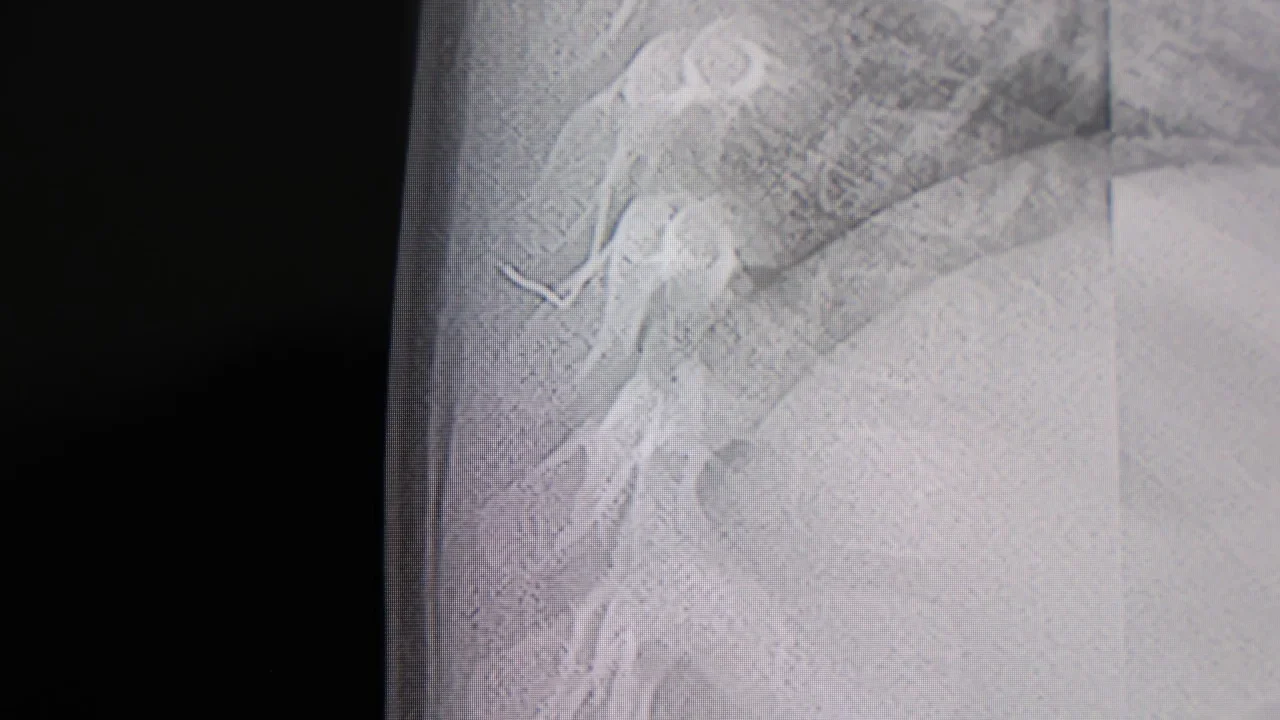

Alınan bilgiye göre, Kahramanmaraş'ta farklı ortopedi, çocuk cerrahisi ve beyin cerrahisi kliniklerine başvurusu yapılan bir yaşındaki bebeğin, sırt bölgesinde yabancı bir cisim olduğu ancak müdahalenin zor olduğu ve 8 yaşına kadar beklenmesi gerektiği bildirildi. Aile, bebekleri için son olarak HG Hospital'e başvurdu. HG Hospital Beyin ve Sinir Cerrahisi Uzmanı Prof. Dr. İdris Altun tarafından yapılan tetkiklerde, yabancı cismin cilt altında, omurilik kanalına yakın bir bölgede olduğu ve akciğer zarına doğru ilerlediği belirlendi. Hasta, genel anesteziye alınmadan, lokal anestezi ve sedasyon eşliğinde ameliyata alındı. Yapılan müdahalede yabancı cisim tamamen çıkarıldı. Çıkarılan cismin, ince zımba teline benzer metal bir tel olduğu ve yaklaşık 2 santimetre uzunluğunda bulunduğu tespit edildi. Hasta, aynı gün taburcu edildi.

"Akciğer zarına doğru ilerleyen bir yabancı cisim tespit ettik"Konuya ilişkin açıklama yapan Prof. Dr. İdris Altun, "Sırtında yabancı bir cisim olduğu söylenmiş ancak çıkarılamayacağı ve 8 yaşına kadar beklenmesi gerektiği ifade edilmişti. Bize başvurduğunda yaptığımız tetkiklerde, cilt altında, omurilik kanalına çok yakın ve akciğer zarına doğru ilerleyen bir yabancı cisim tespit ettik. Hastamızı tamamen uyutmadan, lokal anestezi ve sedasyon eşliğinde müdahale ederek lezyonu tamamen çıkardık. Çıkardığımız cismin ince zımba teline benzer, yaklaşık 2 santimetre uzunluğunda metal bir tel olduğunu gördük. Bu yabancı cisim alınmasaydı, bölgede enfeksiyon gelişebilirdi. Enfeksiyon sonucu omurilik kanalında ciddi hasarlar oluşabilir, çocuk büyüdükçe cismin hareket etmesine bağlı olarak omurilikte zedelenmeler meydana gelebilirdi. Ayrıca yana doğru ilerleyerek akciğer zarına ve akciğere batma riski vardı. Bu da enfeksiyona ve ilerleyen süreçte tümörle karışabilecek tablolara neden olabilirdi. Şu an hastamız gayet sağlıklı. Gerekli kontrolleri yaptık ve aynı gün taburcu ettik" dedi.